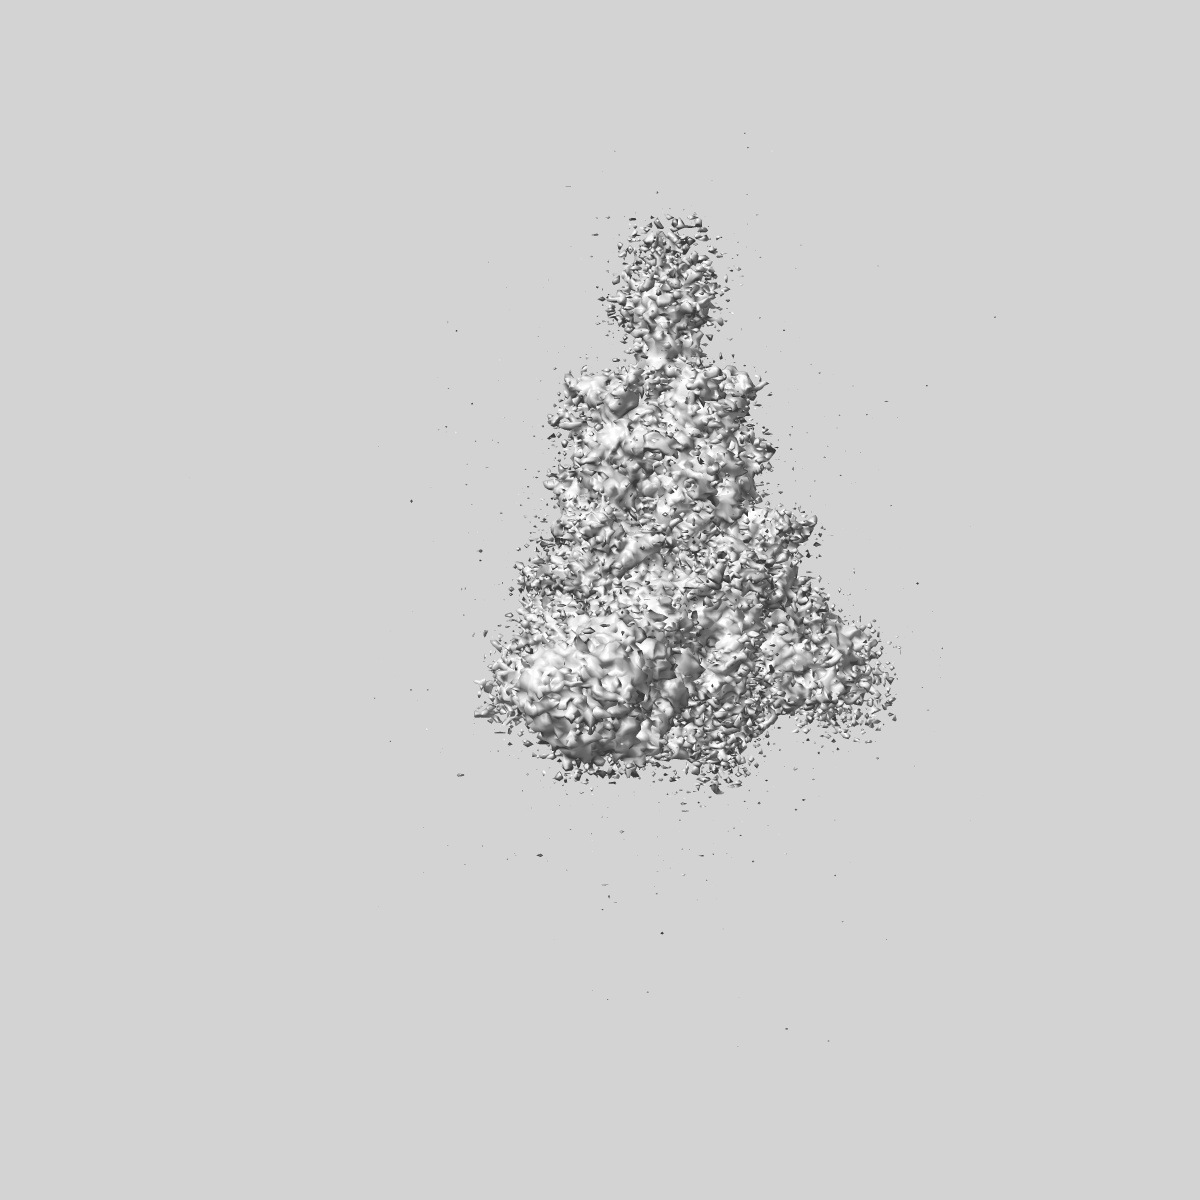

SARS-CoV-2 Wuhan Spike ectodomain in complex with NHP polyclonal antibody NVX-NHPSA5 (NVX-CoV2373/rS-Beta immunized)

Single-particle4.5 Å

Sample: SARS-CoV-2 Wuhan spike ectodomain in complex with NHP polyclonal antibody NVX-NHPSA5